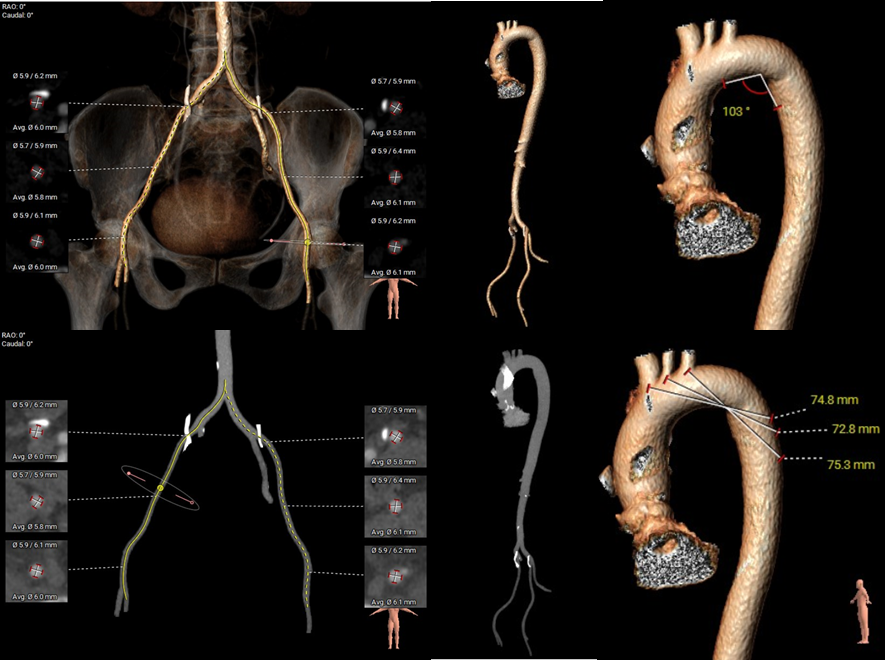

外周血管及主动脉弓解剖:

主动脉弓角度与宽度可,心脏水平夹角46°,非横位心;外周血管内未见明显钙化,双侧入路血管内径良好,整体入路血管条件较好。